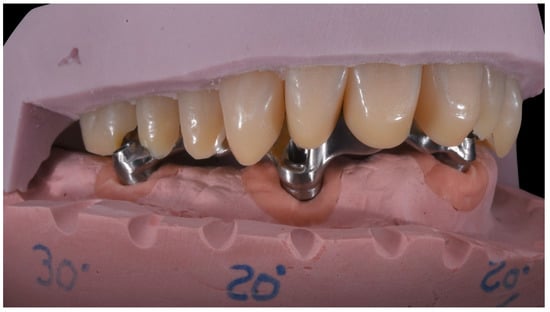

Angled Screwdriver Solutions and Low-Profile Attachments in Full Arch Rehabilitation with Divergent Implants

2. Report and Protocol